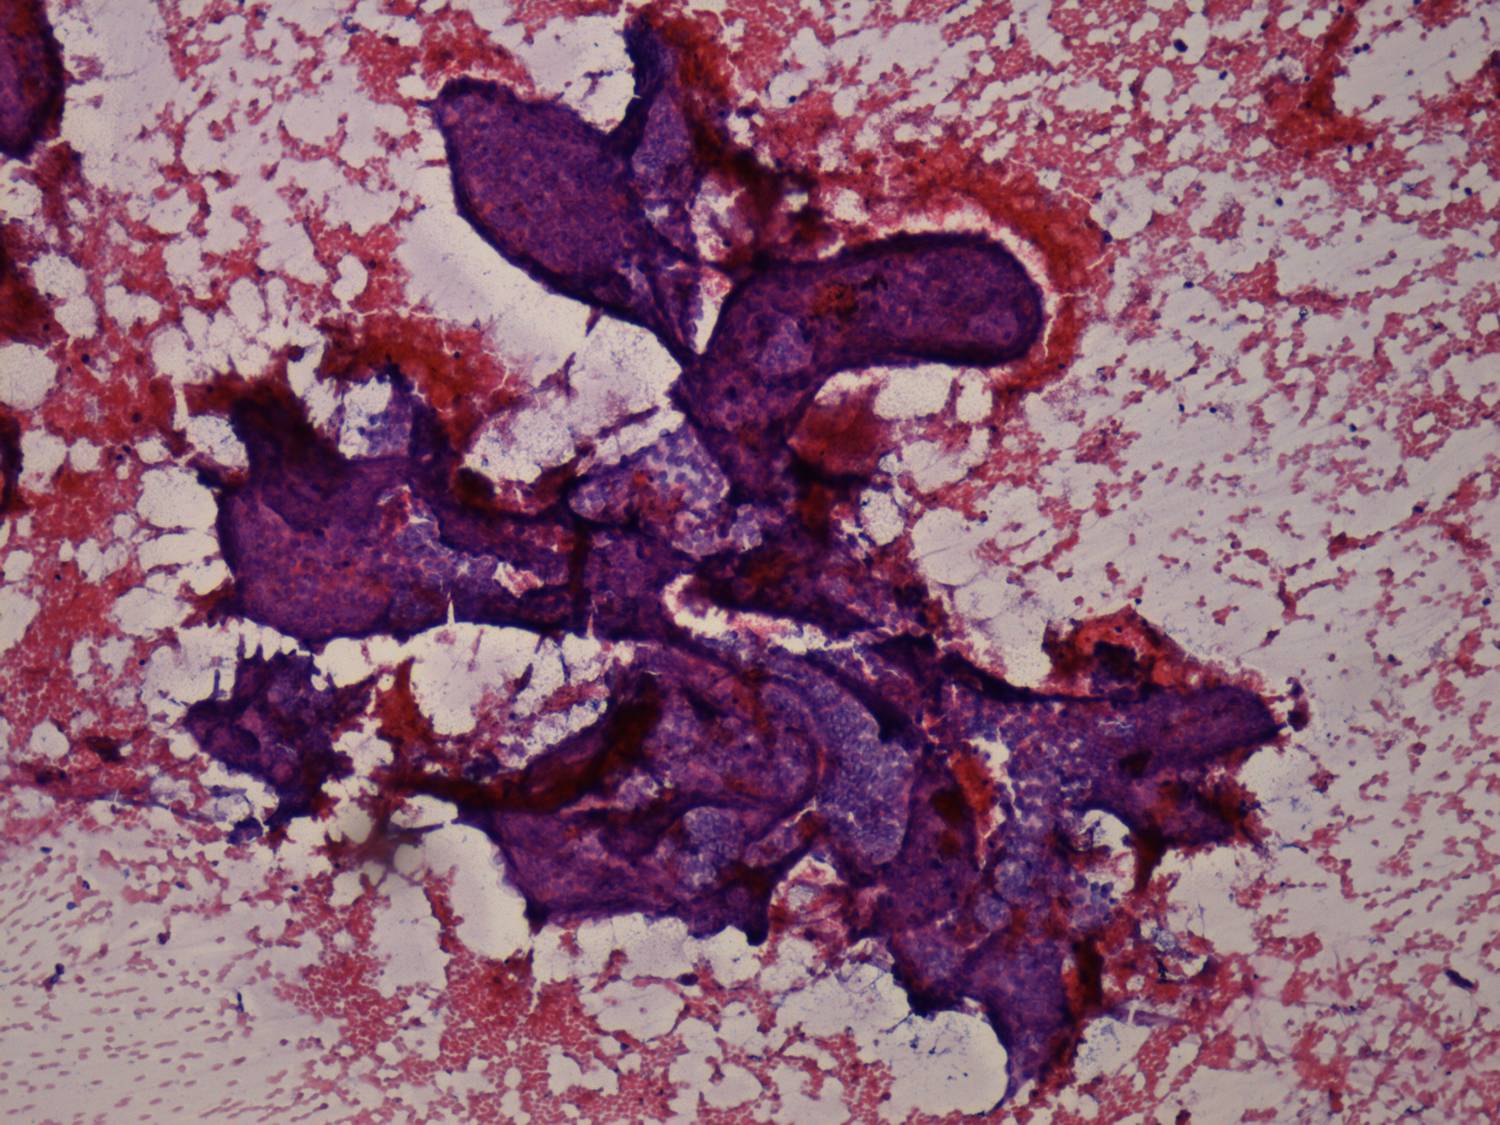

Papillary clusters are three-dimensional structures. They may be arborizing. In the case of a papillary carcinoma, the edge of these clusters are smooth. There is no or only limited tendency of cells to dissociate. Within the papillary groups nuclear crowding and overlapping can be observed.